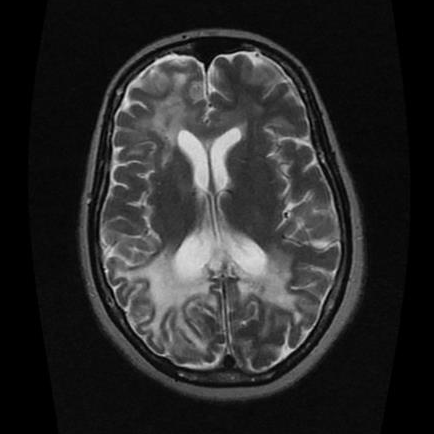

• Asymmetric, multi-focal, bilateral lesions - really anywhere but key place is subcortical U fibers

• T1: hypointense

• T2: hyperintense

• No enhancement on contrasted studies

• Patchy areas of restricted diffusion